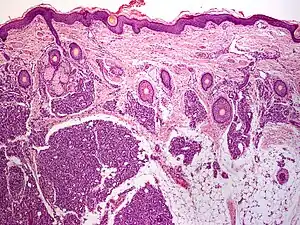

A tufted angioma (also known as an "acquired tufted angioma," "angioblastoma," "angioblastoma of Nakagawa," "hypertrophic hemangioma," "progressive capillary hemangioma," and "tufted hemangioma"[1][2]) usually develops in infancy or early childhood on the neck and upper trunk, and is an ill-defined, dull red flat mark with a mottled appearance, varying from 2 to 5 cm in diameter.[2]: 596